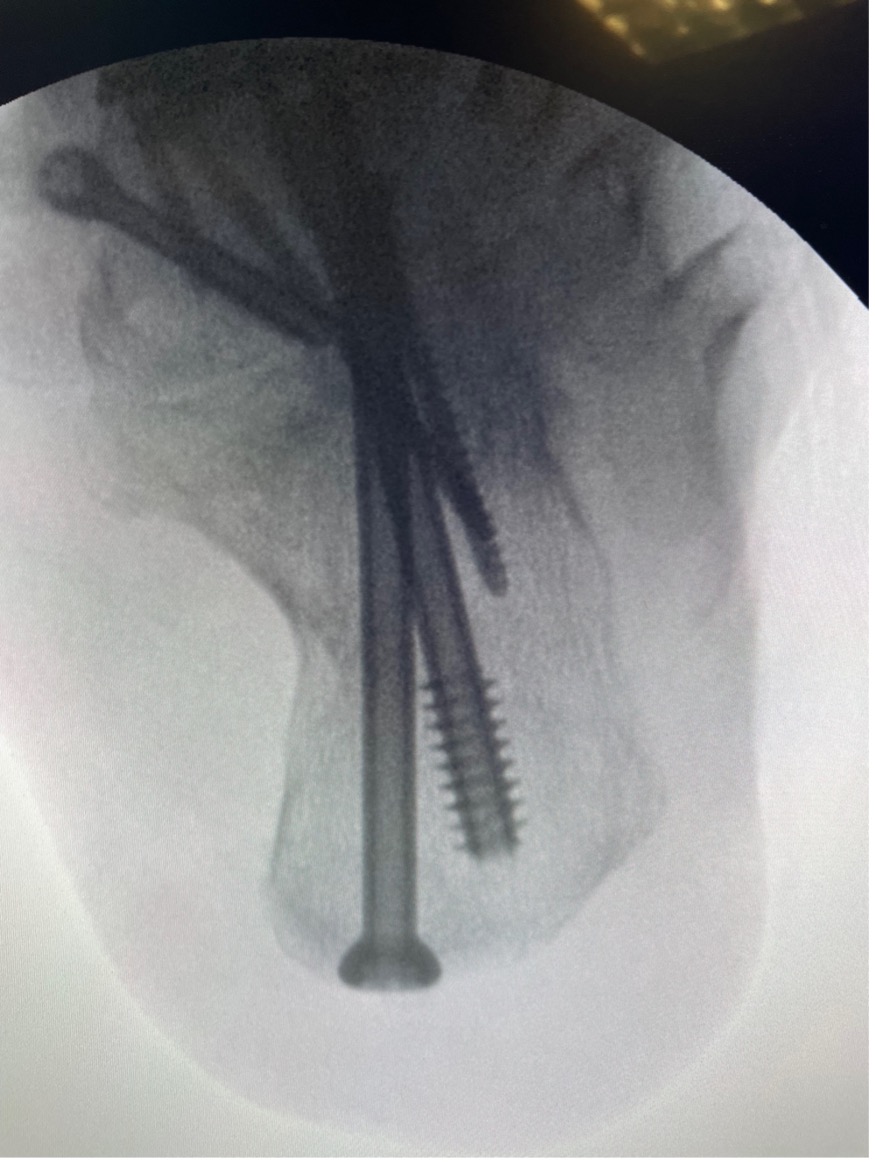

I correct the subtalar joint first, placing my thumb within the sinus tarsi and pulling the calcaneus forward (see photo). Simultaneously, I place the heel into varus. Next, the other hand or assistant drives a guide wire for a 6.5/7.0-mm headless, partially-threaded cannulated screw into the dorsal talus and through the posterior facet. The talus has a notch just proximal to the neck and just distal to the body where this wire is placed. This maneuver allows reorientation of the talus back on top of the calcaneus and corrects the hindfoot valgus. Fluoroscopic AP ankle, lateral foot, and calcaneal axial views ensures appropriate placement. Before definitive fixation, I reduce the talonavicular joint by placing my thumb on the medial side of the talar head and pushing it laterally to reduce peritalar subluxation. With my other hand, I rotate the forefoot into slight valgus to correct any forefoot varus that becomes unmasked.

Engaging the Windlass mechanism and holding the correction, I place a guide wire for a 5.0-mm headless screw from the navicular into the talus. Alternatively, in deformities with severe peritalar subluxation, one may correct the talonavicular joint first, followed by the subtalar joint. Fluoroscopy confirms appropriate placement of the guidewire.

Definitive fixation placement across the subtalar joint should include care to not fracture the fragile navicular tuberosity. Lastly, I place a dorsal neutralization plate over the talonavicular joint. When performing a double arthrodesis, I do not routinely use two screws in the subtalar joint. However, one may choose a second screw placed from the back of the calcaneus, if desired.

One assesses deformity correction by simulating weight-bearing, including evaluation for any residual forefoot varus. If the surgeon identifies forefoot varus, they may elect to perform a calcaneocuboid joint arthrodesis, lifting the lateral column to balance the forefoot. Final fluoroscopy images check the appropriate placement of hardware. This technique guide did not discuss the use of biologics or autograft, but I do routinely utilize some form of biologic to aid in arthrodesis.